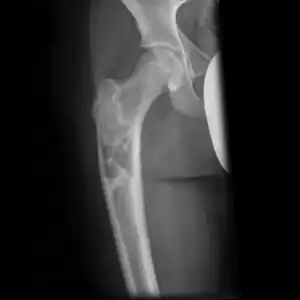

Multloculated cavity in the long bone of the thigh, near the hip. -

Break through simple bone cyst in the long bone of the thigh, near the hip.